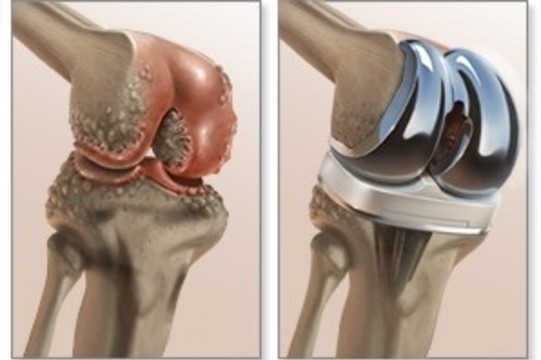

Третья стадия заболевания считается самой сложной. Она приносит сильнейшие боли, которые не прекращаются даже во время сна. На этом этапе развития недуга для больного каждое движение в суставе мучительно. Справиться с артрозом третьей стадии достаточно сложно, консервативные способы лечения обычно уже не оказывают эффекта, поэтому проводится операция по замене всего сустава или его частей.

В запущенных и особо тяжелых случаях врач может назначить органосохраняющее хирургическое вмешательство либо эндопротезирование. В первом случае рекомендуются, как правило, следующие типы вмешательств:

Все они направлены на возобновление суставной функции и сохранение хрящевой ткани. При сильном разрушении суставной структуры поврежденный участок заменяется эндопротезом. Эта процедура называется эндопротезированием и применяется, когда лечение гонартроза уже бесполезно.

На поздних стадиях артроза, когда консервативные методы лечения уже не приносят необходимых результатов, помочь может только хирург. Оперативное лечение артроза обычно предполагает эндопротезирование, то есть замену пораженного сустава на искусственный.

При неэффективности комплекса лекарственной и физиотерапии, ЛФК, стойком болевом синдроме и необратимой деформации суставов с ограничением подвижности, пациенту могут предложить операцию по замене сустава (эндопротезирование, рис. 5).